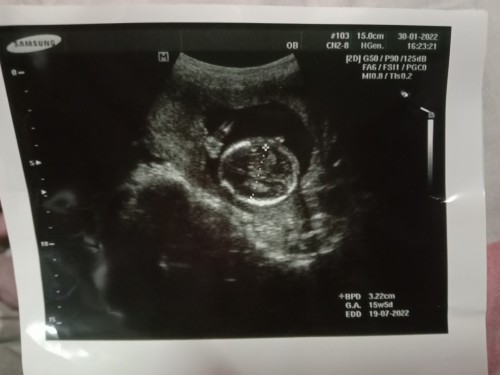

อัลตร้าซาวด์ 15w

พอรู้ไมคะ ส่วนไหนแขนส่วนไหนขา กลมๆนี้เป็นอะไรคะ #ขอบคุณล่วงหน้านะคะ #ขอบคุณสำหรับคำตอบค่ะ #อัลตร้าซาว

อันนี้น่าจะเป็นหัวน้องค่ะ